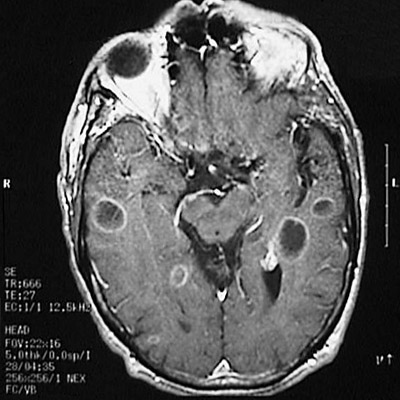

| This magnetic resonance imaging (MRI) scan of the head in transverse (axial) view demonstrates cysticercus cysts of the brain which have dark cystic centers and distinct bright borders with gadolinium enhancement. This patient presented with seizures. |